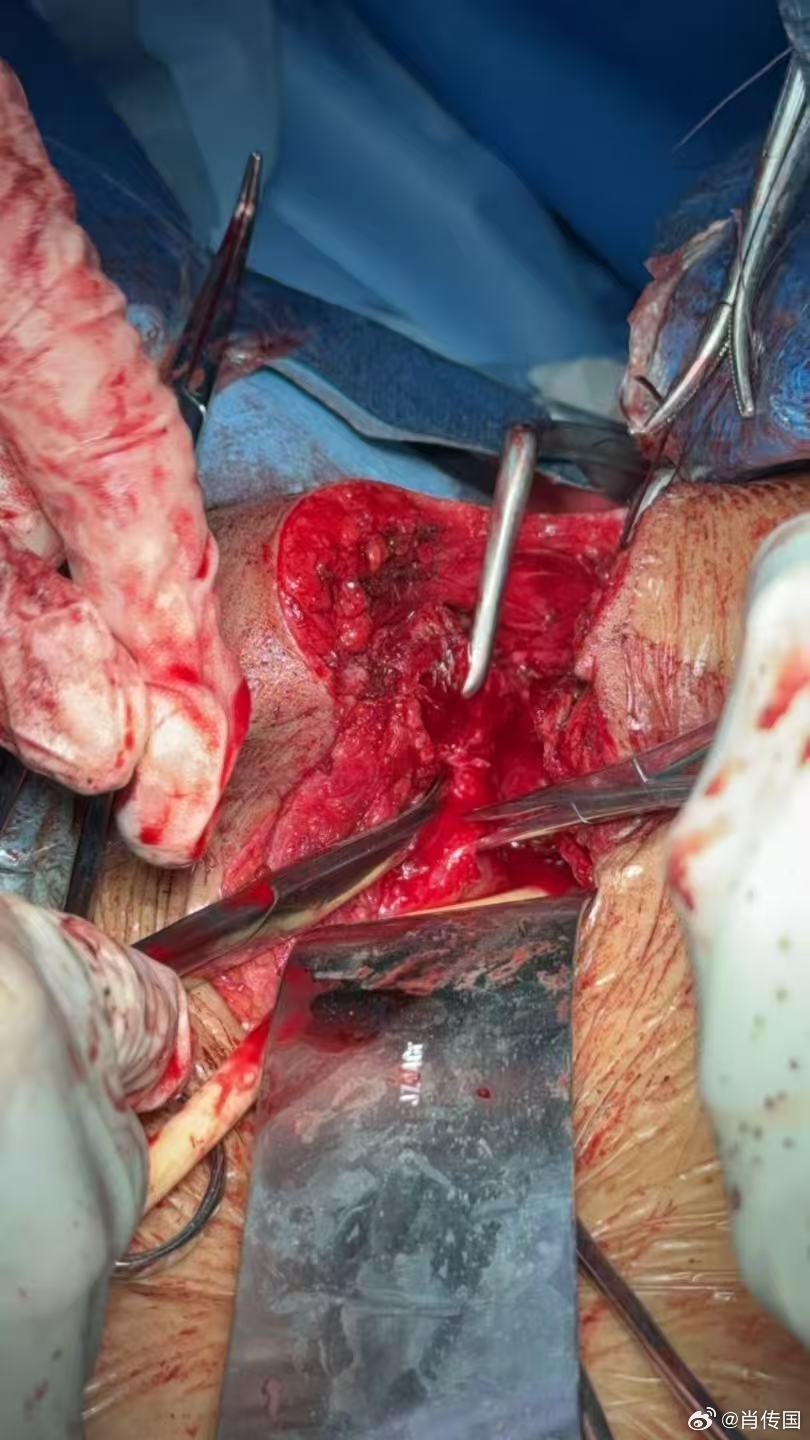

我因肖氏反射弧神经泌尿外科出名,但我的专业实际是整形泌尿外科,作为美国泌尿外科学会Fellow,在最有名的美国泌外整形专科学习工作了二年,回国后除了男女变性没法作,作了无数极端困难泌尿生殖系整形手术,下面这例的复杂困难程度可进入前五吧:介绍一例某省级医院转诊的少见的复杂膀胱瘘,主要给医学同行们参考。7年前因车祸骨盆严重多发骨折,请上海某知名医院骨科专家急会诊手术内固定骨盆。因出血严重,骨盆固定耗时甚长,故仅上尿管未探查处理膀胱等盆腔器官。术后数月出现左腹股沟和会阴部直肠皮肤瘘(耻骨骨拆刺破所致),在外院修复成功。后又发现右会阴大阴唇中上段外侧尿瘘。在外院曾试行经膀胱会阴瘘修补,太过复杂而放弃,转来我院。 经二次手术,治愈。